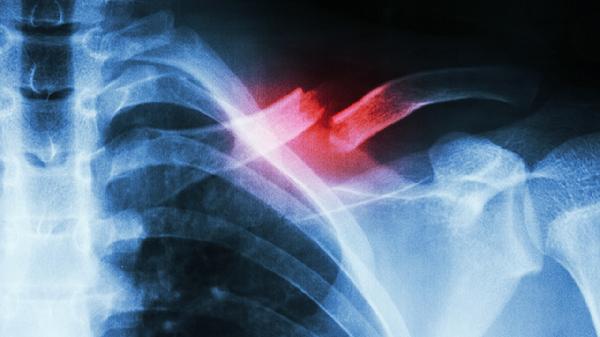

1、肋软骨炎

肋软骨炎是肋骨与胸骨连接处软骨的炎症反应,常表现为局部压痛和肿胀。疼痛可能因咳嗽、深呼吸或按压加重。该病多与劳损、外伤或病毒感染有关。治疗以休息、热敷和非甾体抗炎药为主,如布洛芬、双氯芬酸钠、塞来昔布等。